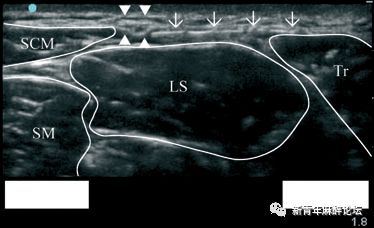

(注:超声引导副神经阻滞图像,SCM:胸锁乳突肌;LS:肩胛提肌;TR:斜方肌;SM:中斜角肌。注意图片深度为1.8cm,四个三角所指为副神经)